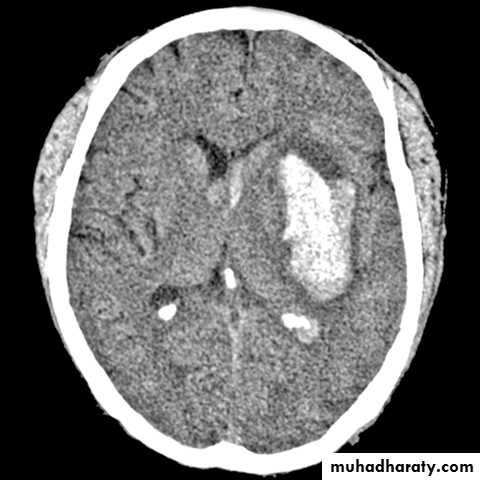

the principle imaging for ICH is CT scanning

Significant volume of intraventricular blood is a poor prognostic indicator.

The presence of hydrocephalus is associated with a poor outcome.

. Larger hematomas have a worse outcome.